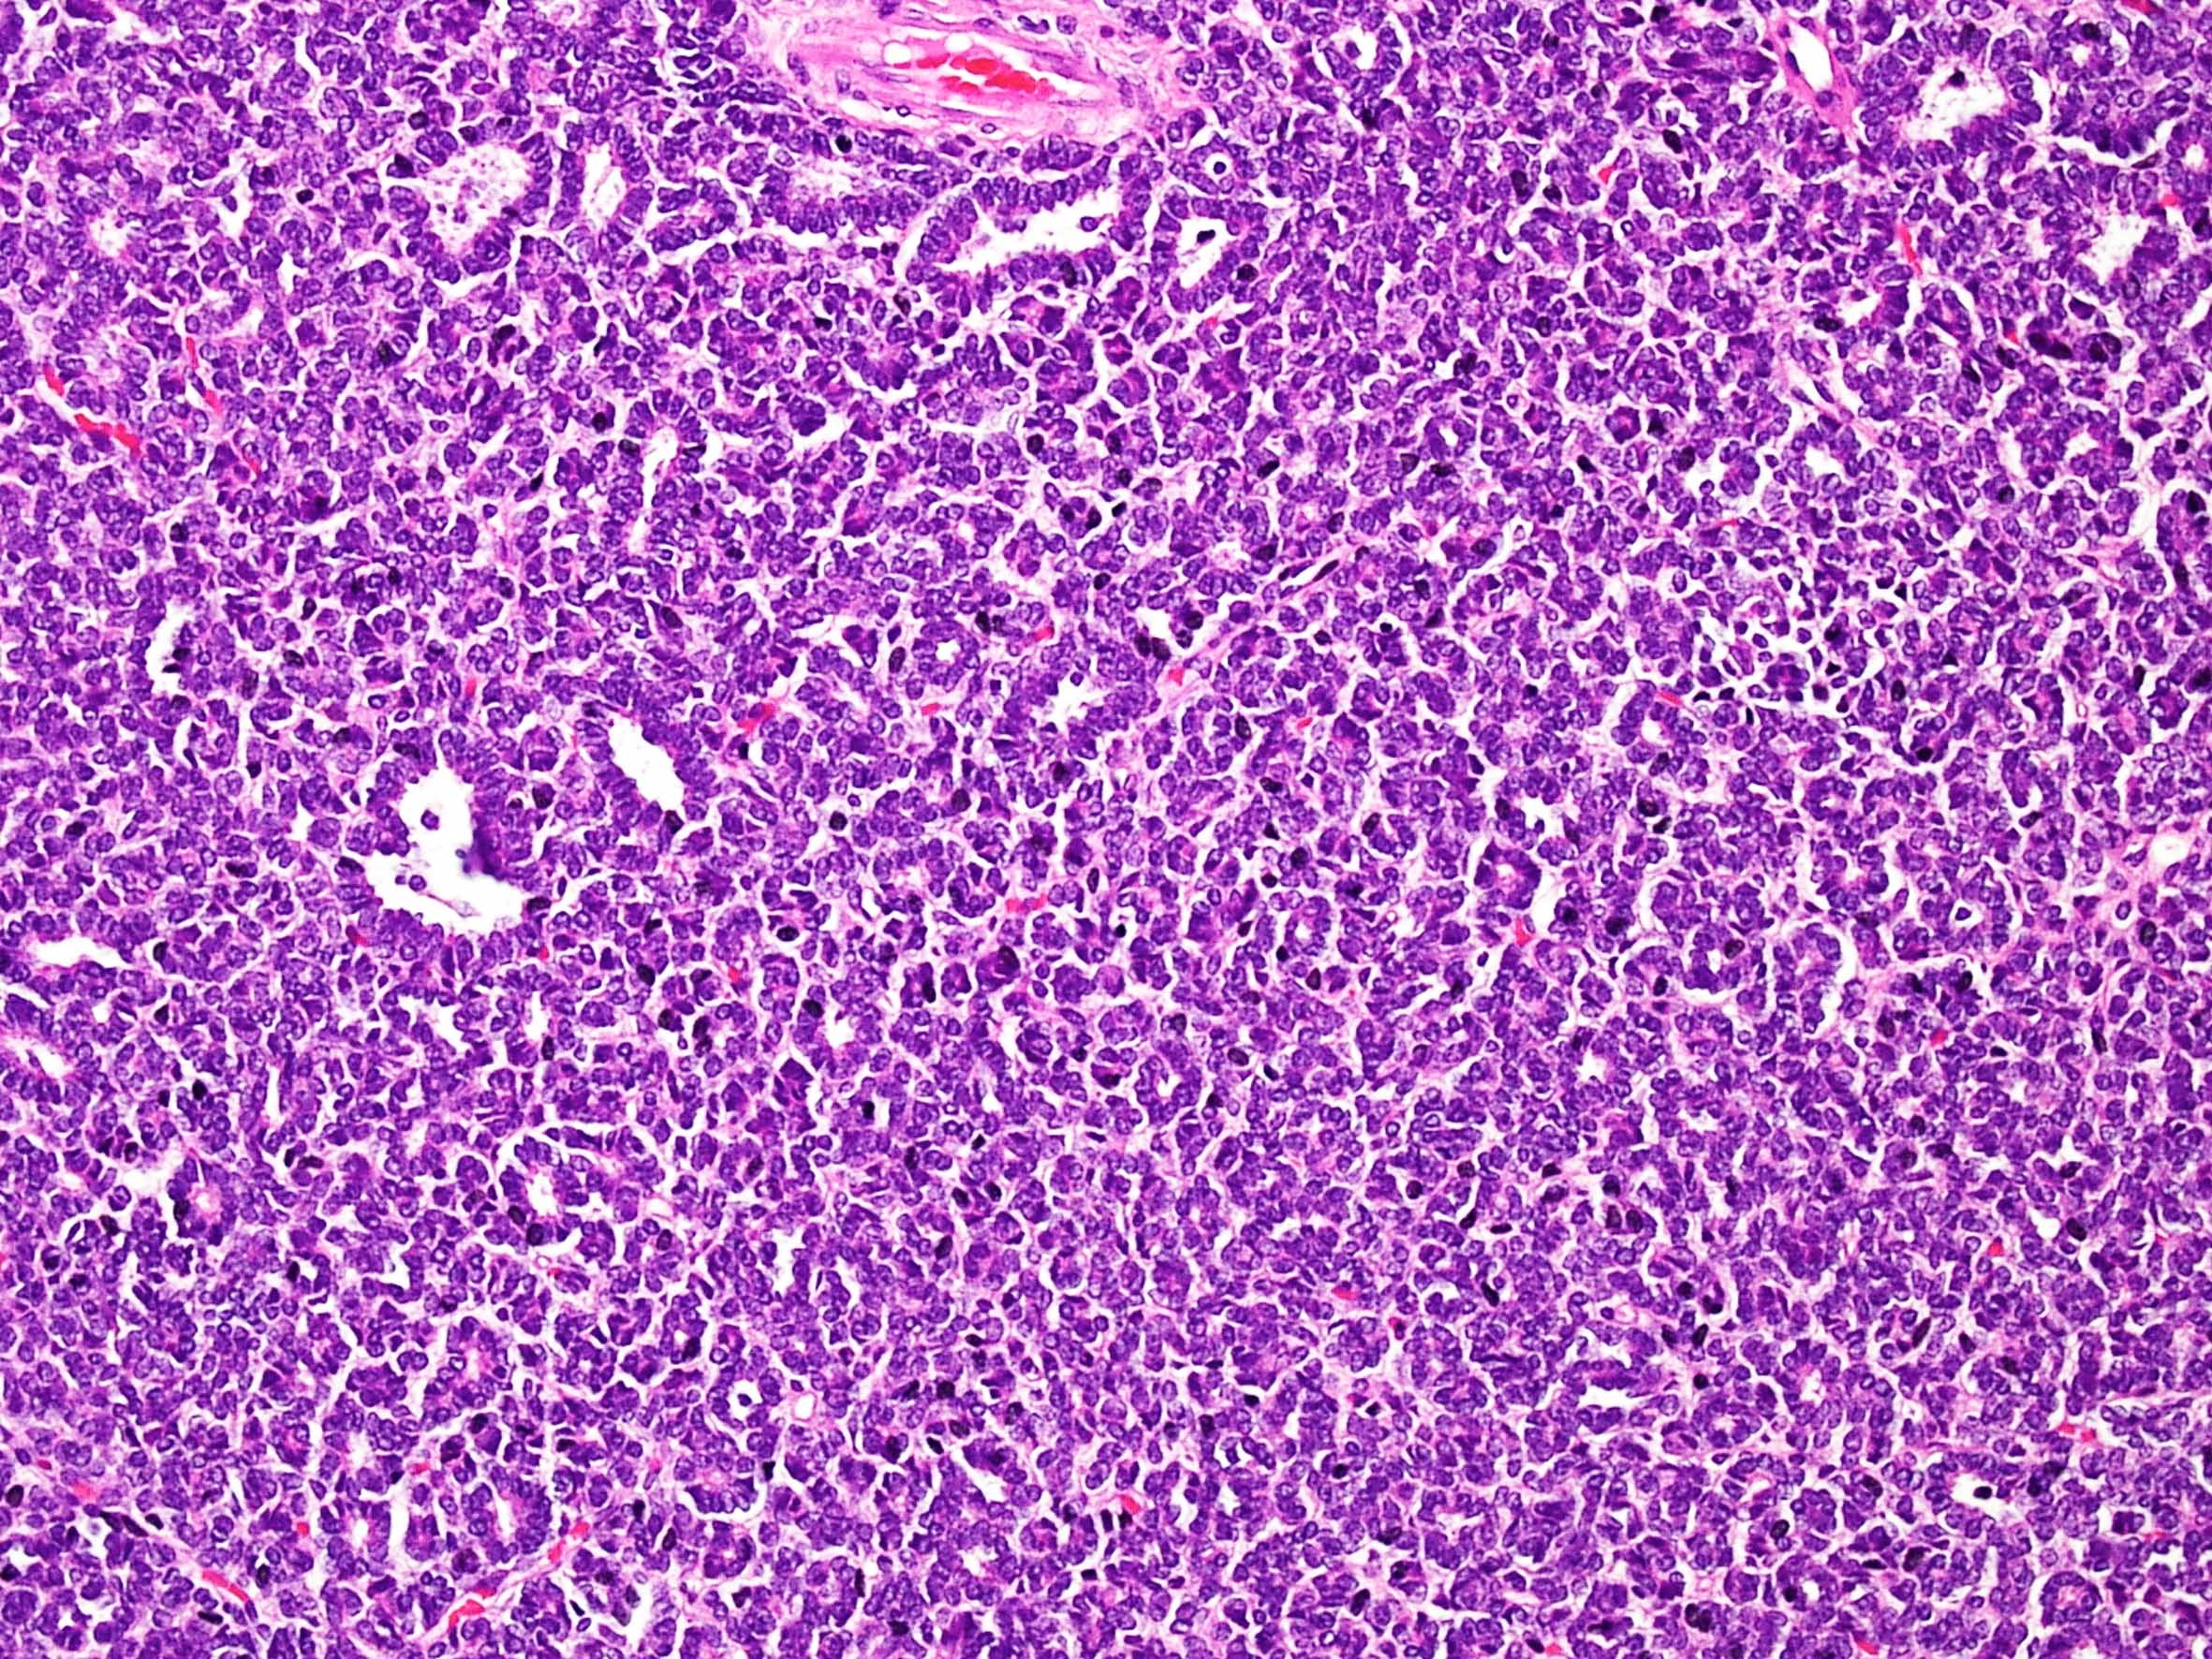

Metanephric adenoma